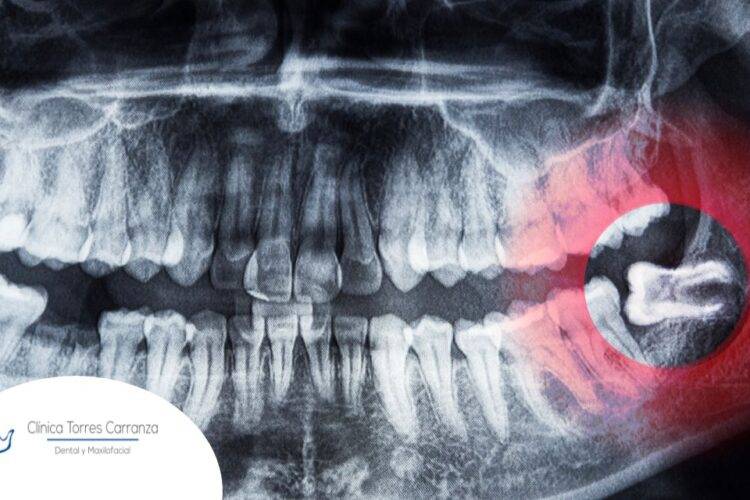

Las muelas del juicio, también conocidas como terceros molares, son famosas por su potencial para causar molestias y problemas. Una de las…